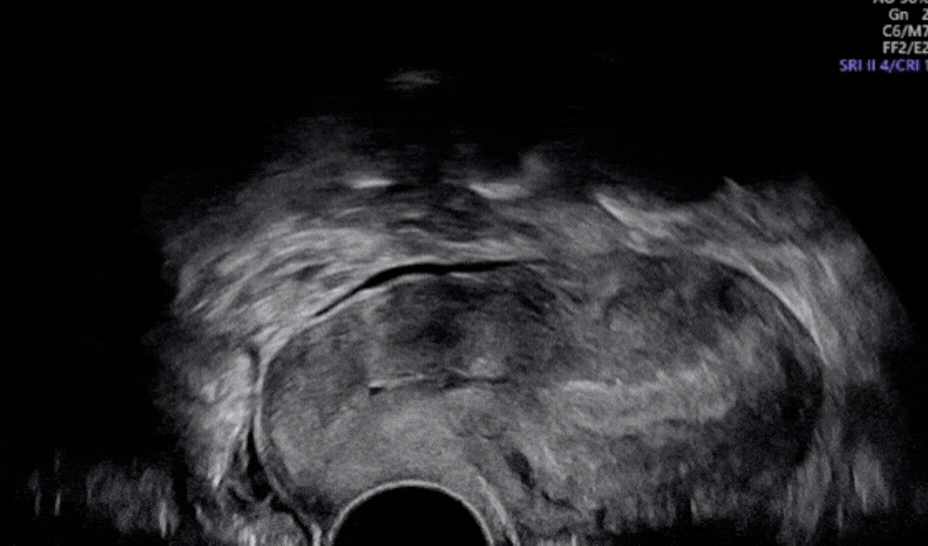

Real-Time Help for Complex Diagnoses

Scanvio Medical is developing an AI-powered assistant designed to support clinicians during pelvic ultrasound exams. The tool analyzes imaging data in real-time to help identify signs of endometriosis - a condition that currently demands a high level of clinical expertise to detect. By embedding intelligent support into a standard procedure, Scanvio could help reduce diagnostic delays and improve patient outcomes.